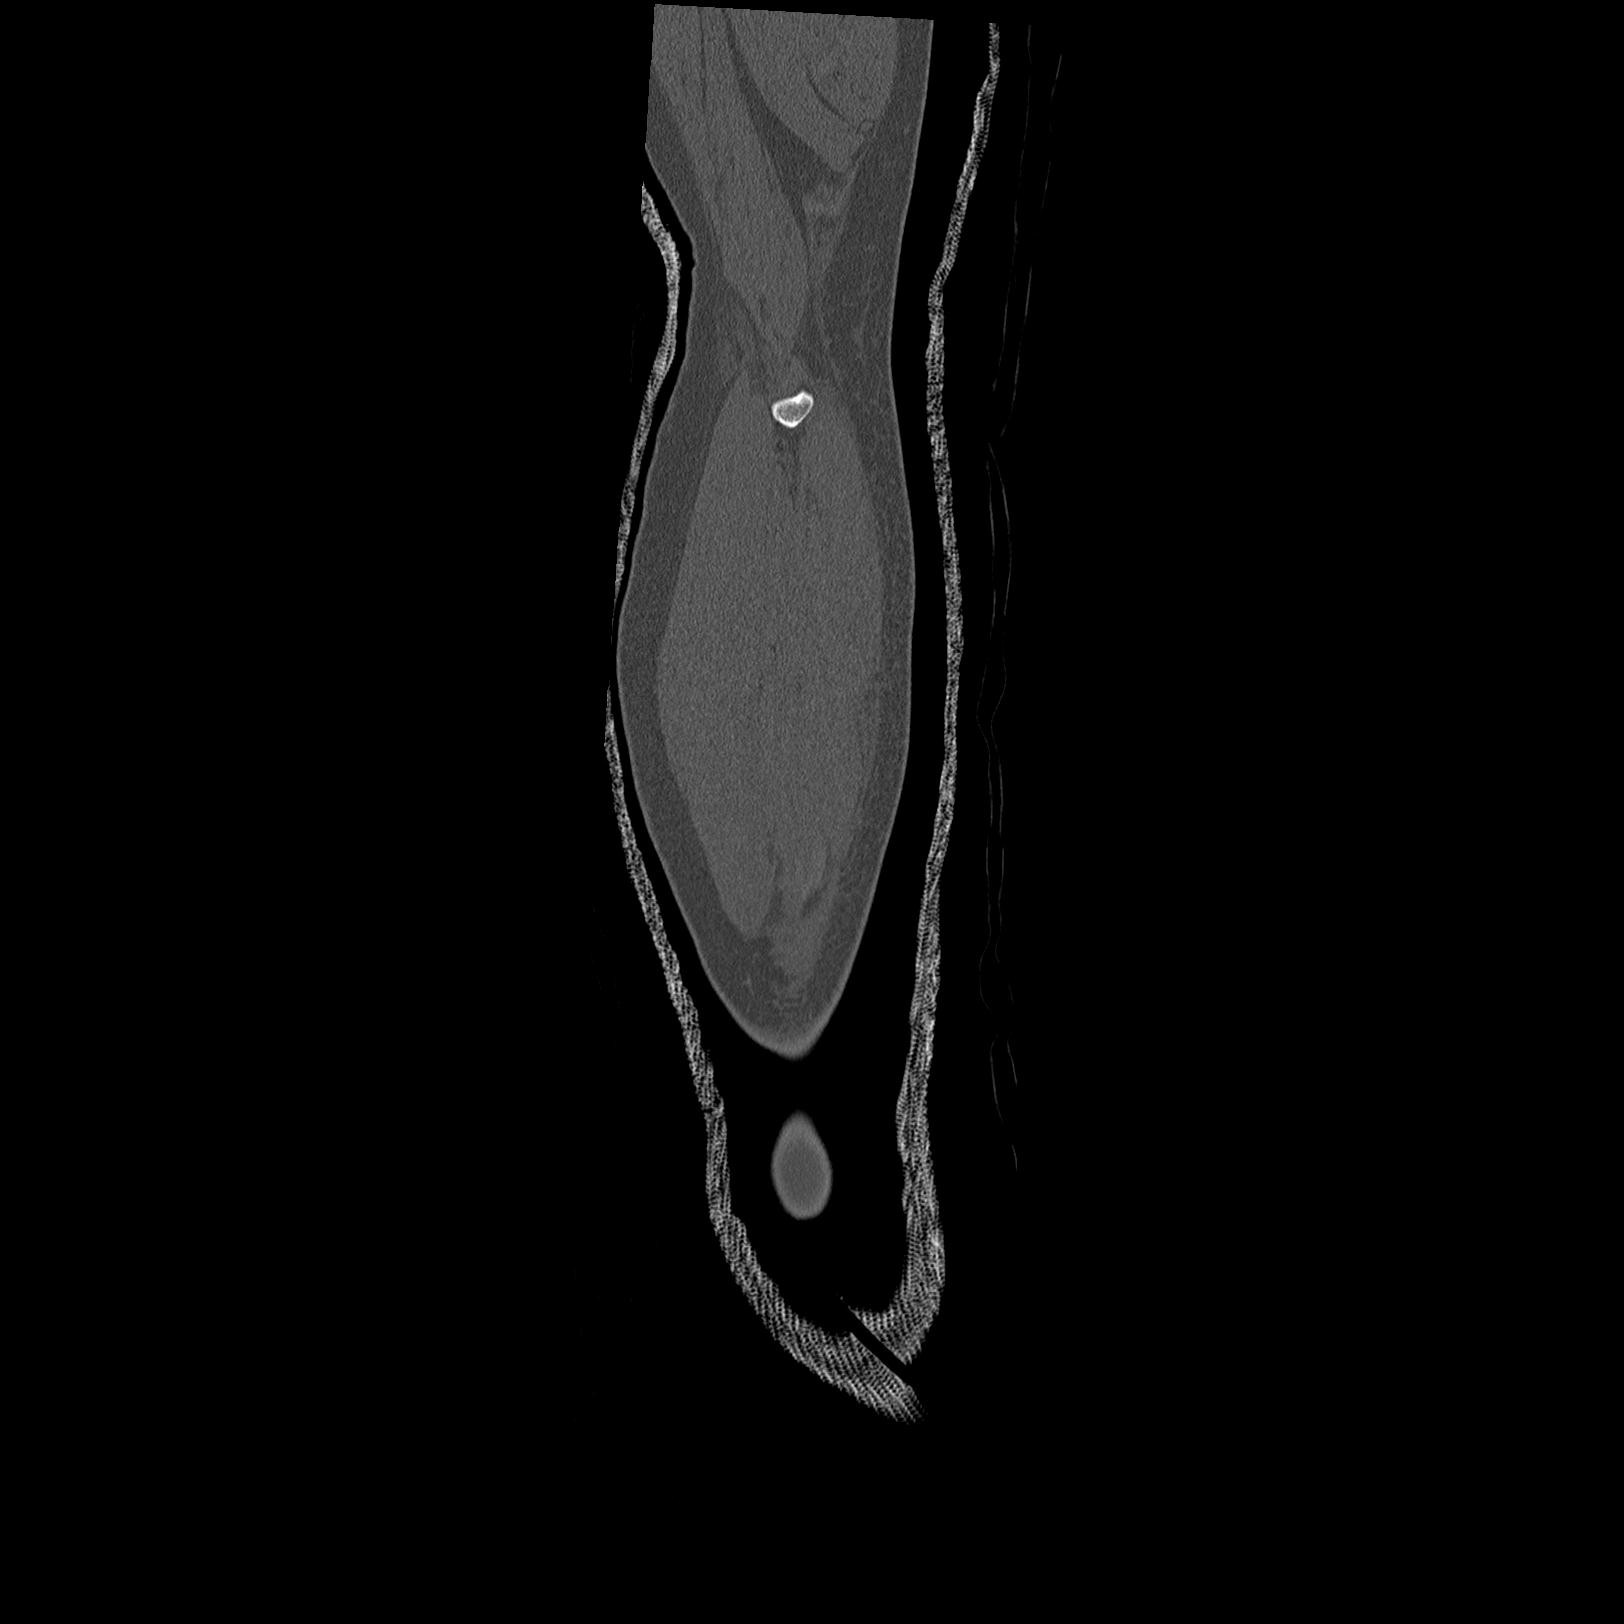

102803 1/12(キウスなし) 1/27 左下腿 4R 30歳女性 左脛骨軸内釘